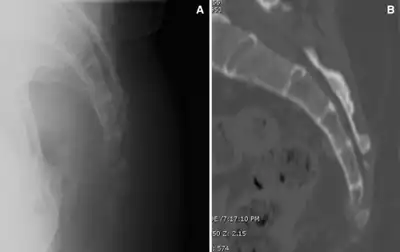

![]() | |

| The location of the coccyx (in red) at the lower aspect of the sacrum of the pelvis | |